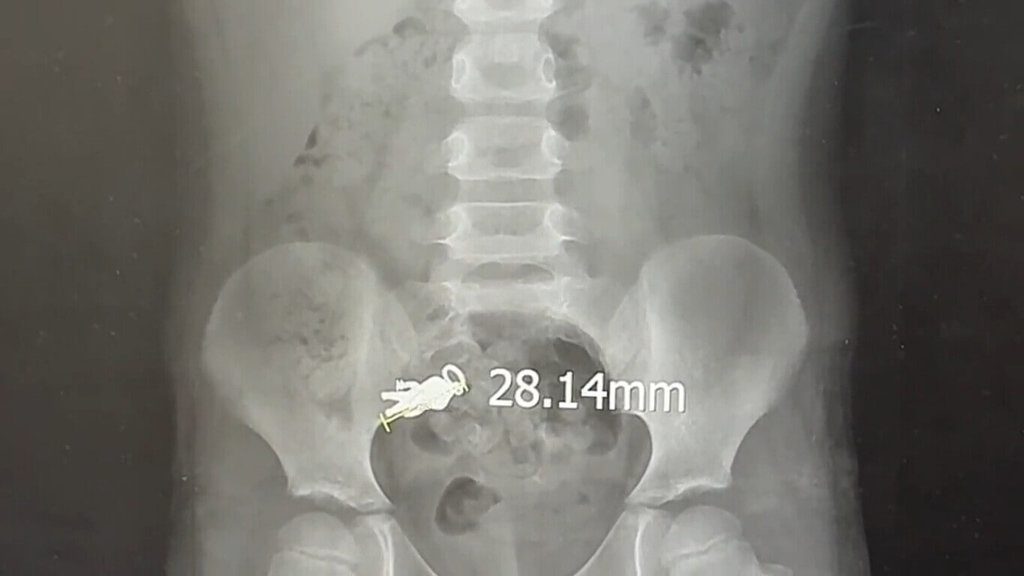

(中央社記者沈如峰宜蘭縣9日電)宜蘭1名7歲男童日前邊看電視邊吃餅乾,誤吞長約2.8公分的「奧特曼」造型吊飾,所幸暫時沒有嚴重的身體影響,醫師建議隨糞便排出。

據了解,男童6日誤吞長約2.8公分、寬1.4公分「奧特曼」吊飾後,因無不適情形,家長希望自然排出體外,當下並未送醫;但到昨天仍未排出,被帶到羅東博愛醫院求診。

羅東博愛醫院小兒科主任謝錦桐今天表示,男童到院後經X光觀察,體內的吊飾已蠕動至腸道,所幸體積不大,加上沒有尖銳部位,暫時不會刺傷腸子,可再觀察2天,隨糞便自然排出即可;若到時仍未排出體外,建議再回診尋求其他方式處理。(編輯:李錫璋)1140909